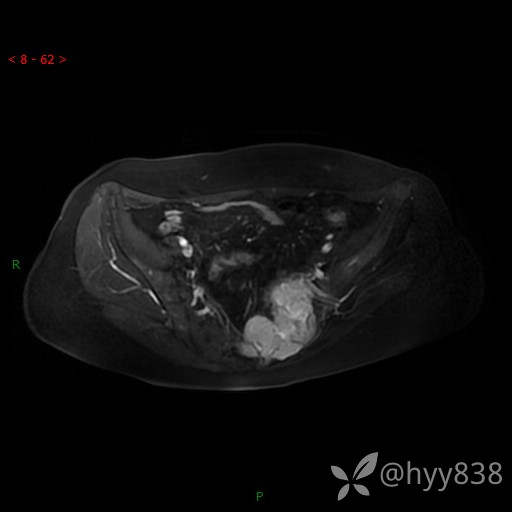

骨盆MRI平扫(T1WI+T2WI+DWI)(外院CT,不能上传)